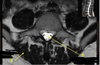

3

4

5

Perfectly

Q

What is letter D?

A